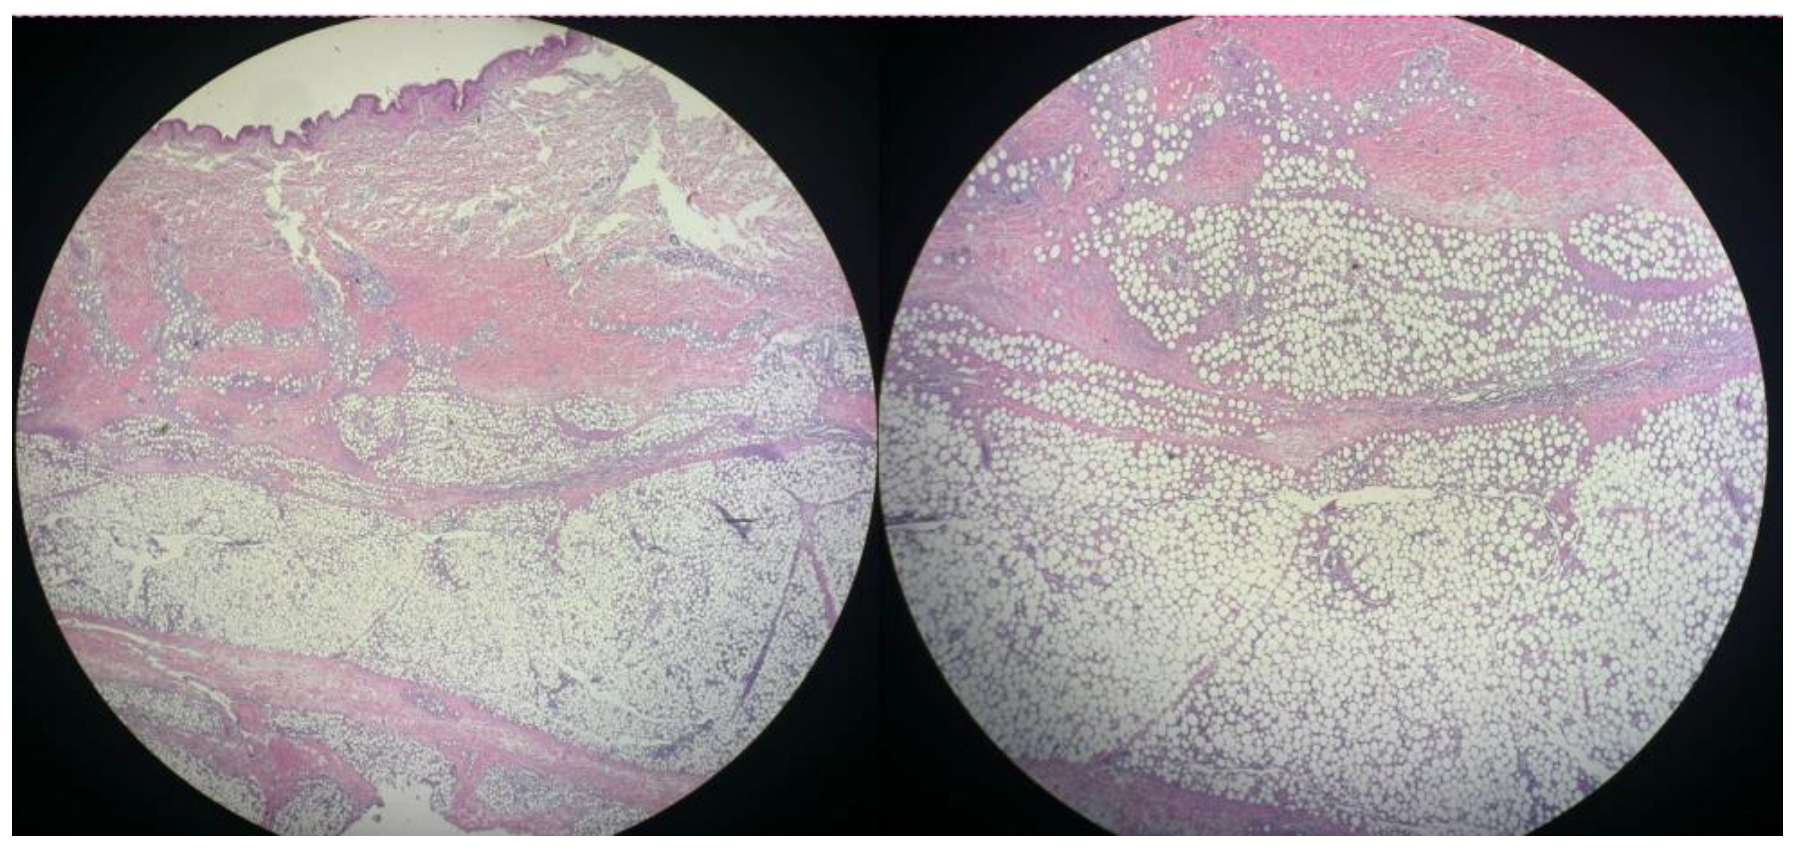

3.2. Histopathology